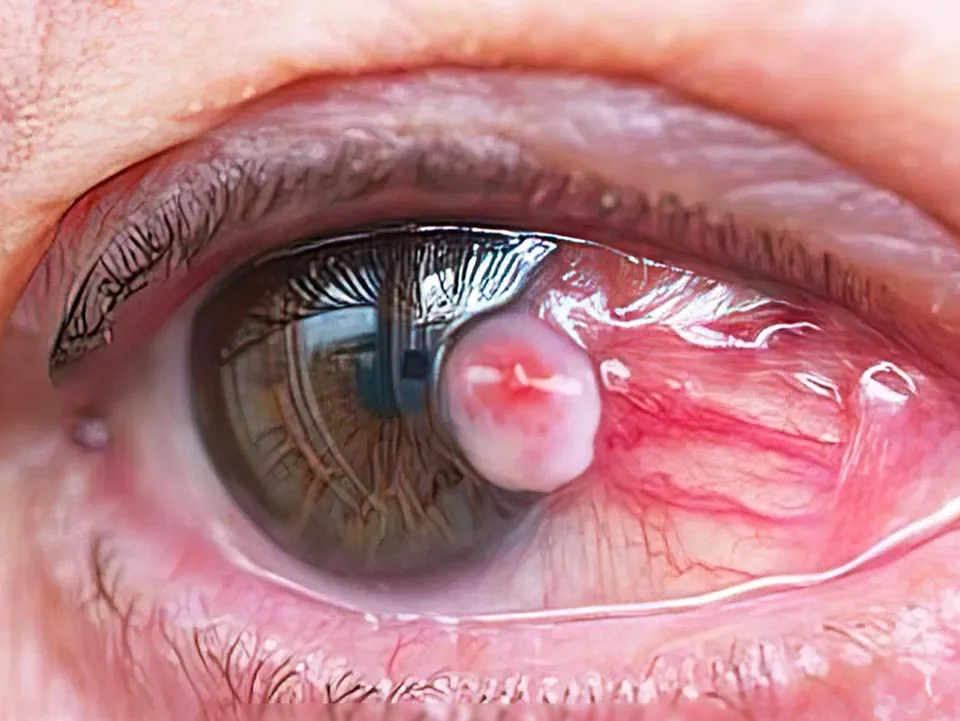

- Pterigión